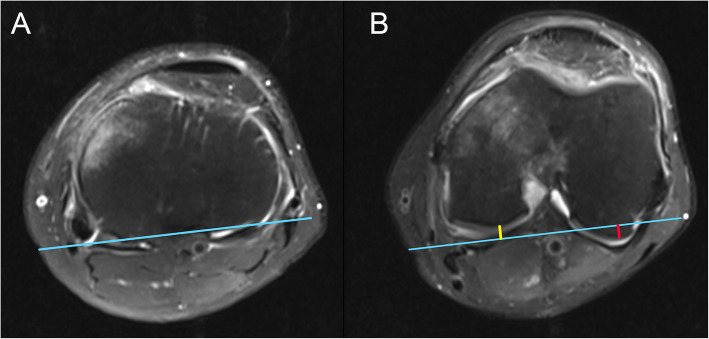

Measurements were performed on the axial plane of MRI to evaluate the translation of the tibial plateau relative to the medial and lateral femoral condyles. According to Alexandre et al. [13], the most posterior points of the femoral condyles and the tibial plateau were determined using axial and sagittal sequences. A line was drawn through the posterior points of the tibial plateau, and the distance from the medial and the lateral condyles to this line was measured as medial PATS and lateral PATS, respectively (Fig. 1). Global PATS was calculated as the mean of the medial and lateral PATS values. The anterior translation of the tibia was expressed as a positive value of PATS, whereas the negative value of PATS indicated the posterior tibial translation.

Fig. 1.

Measurements of the medial and lateral PATS. a Axial plane on MRI showing the line (blue) connecting the most posterior points of the tibial plateau. b After the most posterior points of femoral condyles are determined, the distance from both condyles to the blue line are measured. The length of the yellow line and the red line indicate the medial PATS and the lateral PATS, respectively. In this case, the value of medial PATS is negative (posterior translation), while the value of lateral PATS is positive (anterior translation). PATS, passive anterior tibial subluxation